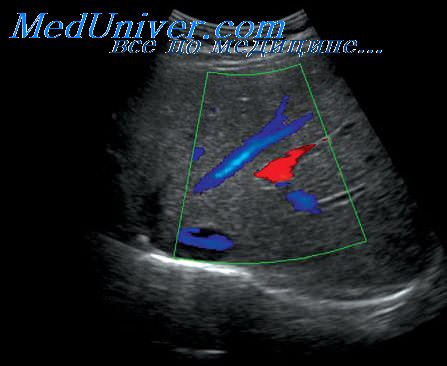

Симптом гиперэхогенных пирамид

Симптом гиперэхогенных пирамид 121 фотографий